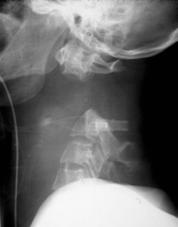

TRAUMA CERVICALA

Incidenta laterala Incidenta

laterala Incidenta

antero-posterioara